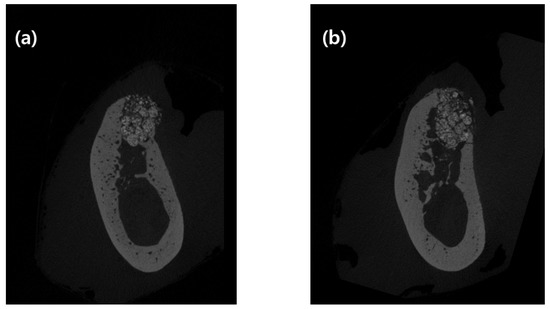

Vertical distance between the buccal and lingual crests and ridge width at 1, 2, and 4 mm from the lingual alveolar crest (Bw1, Bw2, and Bw4, respectively) using 2D data, and bone morphometric analysis using 3D data, are shown in Table 1. Vertical distance between the buccal and lingual crests was 1.28 ± 0.41 mm in the control group and 0.53 ± 0.37 mm in the test group, which was statistically significant (p = 0.028).

Bw1, Bw2, and Bw4 were 4.46 ± 0.73, 5.88 ± 1.10, and 6.89 ± 0.81 mm in the control group and 4.72 ± 0.83, 5.22 ± 1.35, and 6.25 ± 1.43 mm in the test group, respectively. There was no statistically significant difference between the two groups with respect to radiographic bone width.

The BV/TV value was 56.41% ± 9.91% in the control group and 57.00% ± 10.13% in the test group. BS/TV was 10.69 ± 1.35 in the control group and 10.21 ± 1.98 in the test group. TbPf was 1.14 ± 1.07 in the control group and 0.49 ± 1.51 in the test group. SMI was 0.60 ± 0.54 in the control group and 0.25 ± 0.80 in the test group. There was no statistical difference between the two groups as per three-dimensional micro-CT analyses.

When performing the experiment using micro-CT images, vertical distance between the buccal and lingual crests showed a statistically significant difference between the control and test groups. This difference is attributed to the applied double-layer membrane not being absorbed, and providing support until the soft tissue healed and hard tissue formed.

Bone volume density (BV/TV), BS/BV, TbPf, and SMI were not affected by the number of membrane layers applied. It might be due to their representation of the inside of the extraction socket. However, the number of membranes applied on top of the extraction socket seems to affect the boundary of extraction socket. Therefore, there was no statistically significant difference in BV/TV, BS/BV, TbPf, and SMI. In Bw1, Bw2, and Bw4 as well, there was no difference between the two groups. Given that the vertical distance between buccal and lingual crests was approximately 1 mm in both groups, the bone graft inside the extraction socket, placed 1 mm from the lingual crest, was almost stable. These results are similar to those of previous studies that investigated volumetric changes [22].